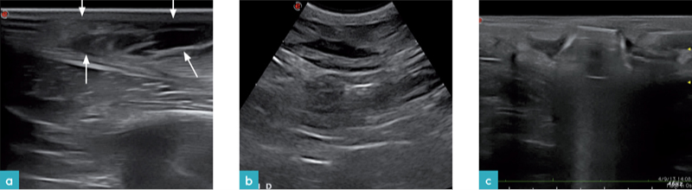

结缔组织炎症的超声影像为皮下组织中弥散分布的低回声局限性病灶,其回声不均匀,边界不规则(图13)。